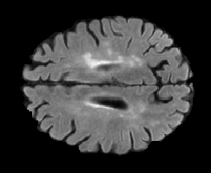

FLAIR

[Uncaptioned image] [Uncaptioned image] [Uncaptioned image]

T1

Ground Truth

Table 2: Segmentation results for all proposed methods, each column represent a different slide in the image, blue areas are regions which were correctly labeled, false positives are shown in green, and false negatives in yellow